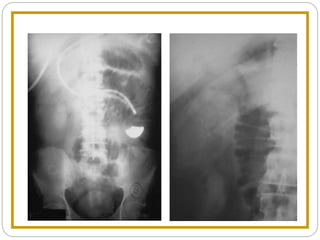

Sentinel Loops

Supine Prone

Localized Ileus Key Features

 One or two persistently dilated loops of large

or small bowel

 Gas in rectum or sigmoid

Localized Ileus